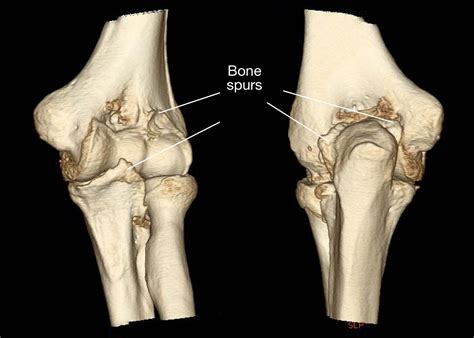

CT Scan Offers a more precise 3D view of the bone structure if the X-ray is inconclusive.

To determine if you have a bone spur elbow, a healthcare professional will typically conduct a physical examination followed by imaging studies. During the physical exam, they will test your range of motion and look for areas of tenderness. Imaging is essential to confirm the diagnosis and assess the extent of the growth.

Diagnostic Tool Purpose

X-Ray The most common method to visualize bone density and identify bony projections.

MRI (Magnetic Resonance Imaging) Provides detailed images of soft tissues, useful for identifying nerve compression or ligament damage.